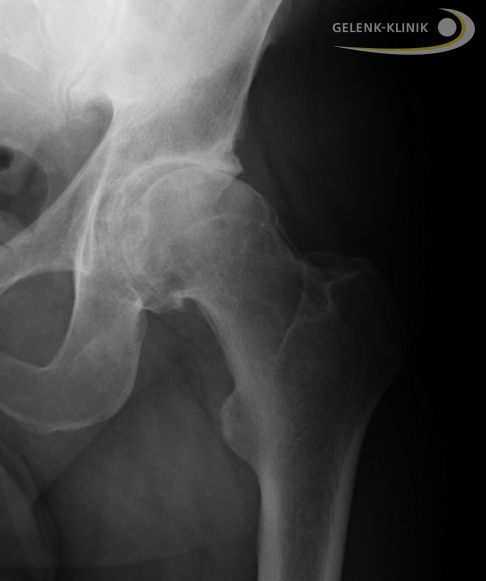

Als Resultat einer zunehmenden Überlastung verändern sich die Knochenoberflächen der Gelenke. Der Knochen unter den Gelenkflächen verstärkt sich. Man bezeichnet diesen Vorgang als subchondrale Sklerosierung. Diese ist im Röntgenbild deutlich sichtbar.

Osteophyten (Knochensporne)

Knochen hat die natürliche Tendenz, einwirkende Gewichtslast auf eine möglichst große Fläche zu verteilen. Aus diesem Grund bilden sich an den Rändern der Gelenkfläche Knochenaufbauten, sogenannte Osteophyten. Osteophyten sind im Röntgenbild sehr gut sichtbar. Sie beschleunigen den Knorpelabrieb im Gelenk zusätzlich. Man kann sie aber nicht einfach im Rahmen einer Hüftarthroskopie abtragen, weil die Osteophyten bei der Anpassung des Hüftgelenks an den zunehmenden Knorpelabrieb eine wichtige Rolle spielen.

Die Röntgenuntersuchung ist die Standarddiagnostik der Hüftarthrose. Das im Stehen unter Belastung aufgenommene Röntgenbild lässt Rückschlüsse auf die verschiedenen Stadien der Hüftarthrose zu. Man spricht hier von einer funktionellen Diagnostik, die die Funktion des Hüftgelenks überprüft. Unter Gewichtsbelastung hält nur die funktionierende Knorpelschicht im Hüftgelenk die beiden beteiligten Gelenkpartner mit einem sichtbaren Gelenkspalt auf Abstand. Je nach Stadium der Arthrose verschmälert sich der Gelenkspalt also bei zunehmendem Knorpelverschleiß immer weiter. Im Stadium 4 der Hüftarthrose ist der Gelenkspalt schließlich ganz verschwunden: Oberschenkelkopf und Hüftpfanne liegen bei schwerer Hüftarthrose direkt aufeinander.

- Ist der Gelenkspalt verschmälert?

- Sind Hüftkopf und Gelenkpfanne normal geformt?

- Ist der Knochen unter dem Knorpel verstärkt (sklerosiert)?

- Ist der Knochen über flüssigkeitsgefüllten Hohlräumen (Geröllzysten) eingebrochen?

- Gibt es freie Gelenkkörper?

- Haben sich Knochenstücke aus Nekrosebezirken (abgestorbenes Knochengewebe) nahe der Gelenkfläche abgelöst (Osteochondrosis dissecans)?

- Verbreitert sich der Knochen im Gelenk durch dornförmige Osteophyten?